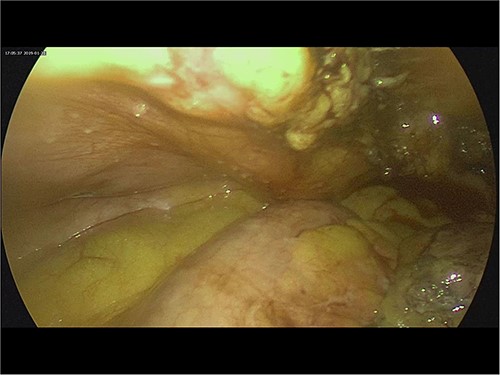

A 24-year-old male was admitted to the General Surgery out-patients clinic with a 2-week history of right iliac fossa pain. The patient had no other associated gastrointestinal symptoms. He had no other significant medical history but had undergone an open appendectomy for perforated appendicitis three months prior to the current presentation. Patient was vitally stable on presentation and the per abdominal examination showed tenderness at the McBurney’s point. A computed tomography (CT) scan of the abdomen revealed thickened and enhanced stump appendix along with adjacent fat stranding and multiple mesenteric nodes; suggestive of SA (Fig. 1). There was also a suggestion of adhesions and mild wall thickening of adjacent caecal wall with no evidence of collections or bowel mass (Fig. 2). Considering the upward trend seen in white blood cell count and the CT report, we planned the patient for a diagnostic laparoscopy. Pre-anaesthesia clearance was obtained.

Intra-operatively, adhesiolysis of dense bowel and omental adhesions were performed. About 3.5-cm appendicular stump was resected (Fig. 3). Micro-nodular peritoneal nodules were noted and resected (Fig. 4). The specimens were sent for a histo-pathology examination. The postoperative period was uneventful with symptomatic relief. The biopsy of the gross specimen of stump appendix described a single white to grey brown soft tissue measuring 3 cm × 2 cm × 0.8 cm with a congested outer surface. The appendicular wall was 0.3 cm thick while the peritoneal nodule was a 2.5 cm × 0.8 cm × 0.5 cm single grey white to yellow soft tissue. Microscopic report of the appendix revealed multiple granuloma composed of epithelioid cells, macrophages, lymphocytes and multinucleated giant cells (Fig. 5). Caseation necrosis was seen in focal areas and with transmural mixed inflammatory cell infiltrate (Fig. 6). The peritoneal nodule showed fatty tissue with infiltration of lymphocytes, plasma cells and neutrophils microscopically.